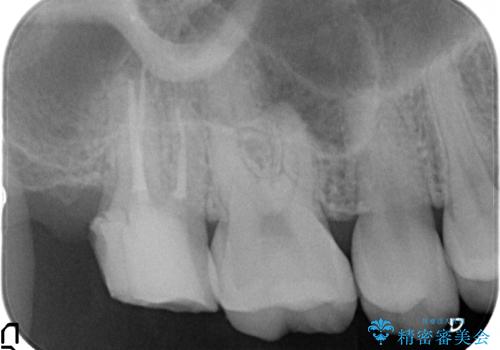

- 右上7の虫歯が大きく、他院にて抜歯と言われたが、なんとか残せないかと当院にいらっしゃった方の症例です。

自発痛の既往および持続痛を認めたため、カリエス除去後根管治療を行いました。

その後オールセラミッククラウンによる補綴を行いました。

- オールセラミッククラウン…¥100,000、仮歯…¥10,000、ファイバーコア…¥20,000費用は治療当時の料金となります